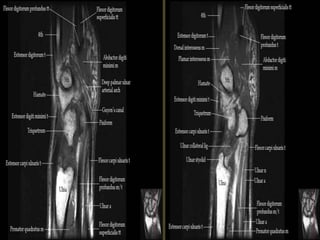

Wrist X-ray Anatomy.

Pronator quadratus.

The transverse carpal ligament (short arrows) extends from the hook of the hamate (long

arrow) to the tubercle of the trapezium (arrowhead), forming the floor of the carpal tunnel.

At the radial aspect of the carpal tunnel, the flexor digitorum tendons are arranged in two

rows (separated by dotted line), the profundus tendons deep to the superficialis tendons. The

flexor pollicis longus tendon (star) is positioned at the ulnar aspect of the tunnel, separated

from the flexor carpi radialis tendon (curved arrow) by a ligamentous reflection of the

transverse carpal ligament. The median nerve is indicated (asterisk). - See more at:

http://radsource.us/palmar-bursae-and-flexor-tendon-sheaths/#sthash.mSFX1u0c.dpuf